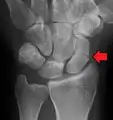

| An X-ray showing a fracture through the waist of the scaphoid | |